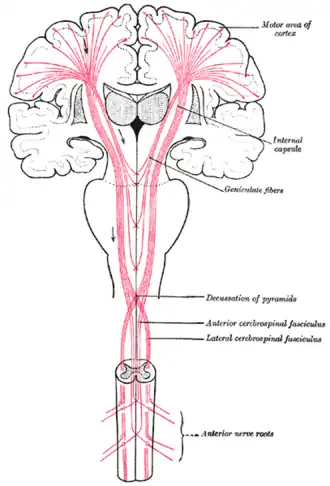

Гистологически область первичной моторной коры отличается от других областей наличием клеток Беца. Слой V первичной моторной коры содержит гигантские (70—100 мкм) пирамидальные нейроны, которые названы клетками Беца. Аксоны этих нейронов идут в контралатеральные моторные ядра черепных нервов и нижние мотонейроны передних рогов серого вещества спинного мозга. Дендриты клеток Беца достигают поверхностного молекулярного слоя, аксоны этих нейронов передают информацию к базальным ганглиям, стволу и спинному мозгу, формируя кортикоспинальный тракт. Стоит отметить, что клетки Беца составляют лишь малую часть кортикоспинального тракта — около 10 % всех нейронов первичной моторной коры[2] и около 2—3% от общего объёма кортикальной проекции для спинного мозга[3]. Несмотря небольшую долю клеток Беца в общем объёме нейронов двигательной коры, они являются чётким маркером, определяющим именно первичную моторную кору[4].

Проводящие пути

Приблизительно 30 % волокон пирамидного тракта берут начало в V слое первичной моторной коры (поле 4), еще 30 % отправляется из премоторной коры (поле 6) и дополнительной моторной области, в которой возникают побудительные сигналы, предшествующие движению, а остальные 40 % — от соматосенсорных областей (теменная доля, поля 3, 2, 1).

Моторный (двигательный) тракт

Моторный (двигательный) тракт